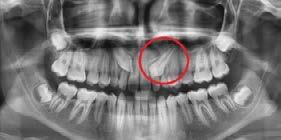

a. Observar radiográficamente las características anatómicas y dimensionales de los caninos superiores e inferiores respecto a dientes adyacentes (Figura 11).

b. Identificar radiográficamente la posición en que se encuentra el canino, respecto a los dientes adyacentes (Figura 12).

El seguimiento del trayecto canino con un estudio radiográfico postero anterior, lateral de cráneo y ortopantomográfico, a partir de la edad señalada anteriormente, también es una herramienta efectiva que permite obtener un diagnóstico inicial, donde podrá observarse si se ha iniciado la reabsorción radicular del canino deciduo e identificar qué

dirección o trayecto está tomando el canino permanente (Figura 18).

Ubicación del canino

Un método sencillo para obtener el diagnóstico de inclusión canina en proceso o declarada, cuando no se realizó un seguimiento desde una edad temprana, será utilizando como herramienta de diagnóstico inicial, una ortopantomografia, donde al trazar puntos, planos y líneas de referencia en estructuras dentocraneales y en el eje longitudinal del canino propiamente, podremos ubicar tridimensionalmente el sitio de inclusión en proceso de formación radicular (estadio del 6 al 9), o definitivo, cuando el ápice se ha cerrado (estadio 10 de Nolla) y el diente no erupcionó8 (Figura 20).